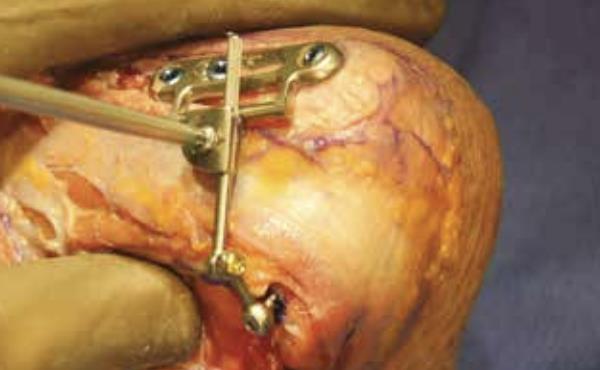

• Base plate positioning

• position the Base Plate on the proximal aspect of the ulna

• Base plate drilling

• drill for bicortical fixation through the sliding slot on the Base Plate using the 2.7mm drill bit, aiming towards the coronoid process and away from the radial notch

• measure using the Depth Gauge for the appropriate length 3.5mm compression screw (Polyaxial Non Locking)

• Axis pin measurement

• insert the corresponding 3.5mm compression screw (Polyaxial Non Locking) using the T-10 Driver

• repeat past two steps for the remaining two compression screw holes of the Base Plate

• Construct alignment

• if the head of the Proximal Locking Screw or the arrow of the Distal Locking Joint are NOT pointing proximally

• loosen the Distal Locking Screw and remove the Distal Connecting Rod to flip the Distal Locking Joint 180° so that its arrow is pointing proximal

• then reinsert the Distal Connecting Rod back into the Distal Locking Joint with the Proximal Locking Screw also pointing proximal

• Inserting the axis pin

• adjust the Distal Connecting Rod to allow the selected Axis Pin to be inserted through the eyelet of the Proximal Connecting Rod and into the humerus

• Locking the axis pin

• use the PROTEAN Pliers to stabilize the Proximal Connecting Rod while fully tightening the Axis Pin using the T-10 Driver